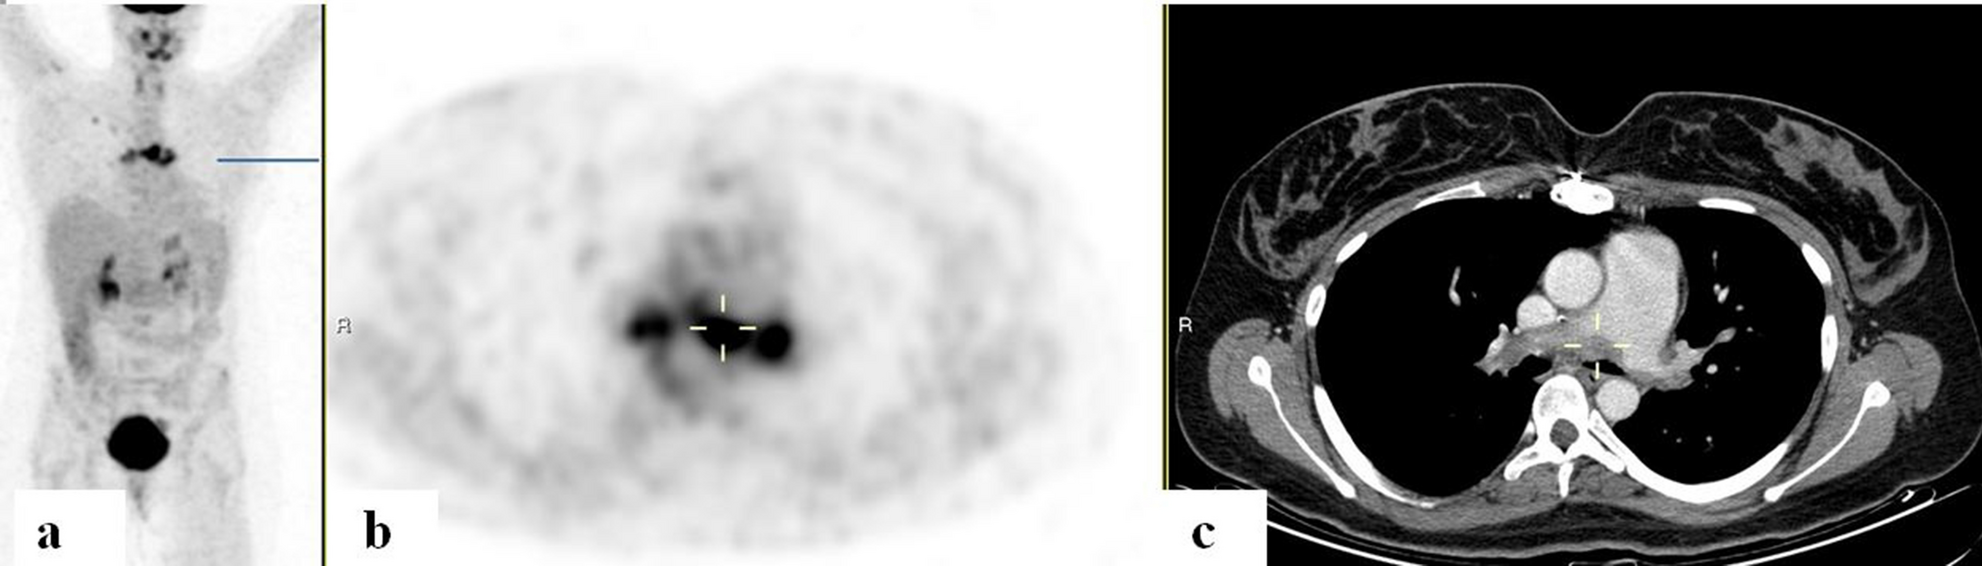

Figure 2

FDG-PET/CT: FDG-PET/CT:Â maximum intensity projection (MIP) (a) a representative PET (b) and CT (c) axial slices. A 31-year-old woman with IgG4-related disease with biopsy proven pulmonary arteritis. PET demonstrated increased uptake along the main pulmonary artery walls (cursers) with corresponding filler defects adjacent to the internal walls of the vessels on CT.